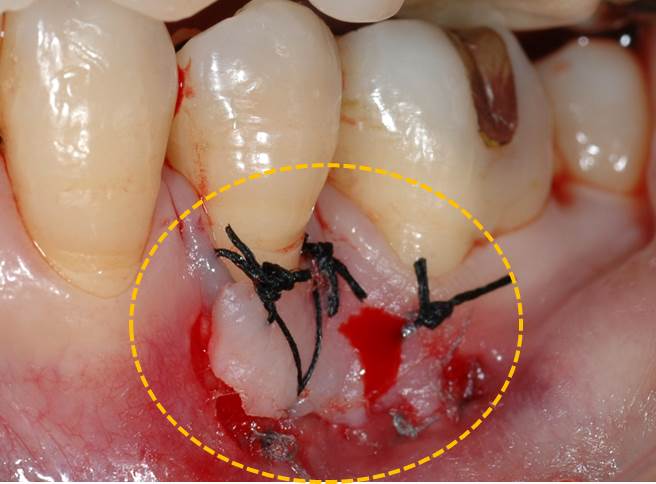

今回は歯周外科処置の中でも最も基本的なフラップ手術の紹介です。

青の歯のオレンジ部分に7mmの歯周ポケットが存在します。

歯肉を剥離して、掃除が終了した状態です。(オレンジの点線部分が失われた歯槽骨)

縫合が終了した状態です。